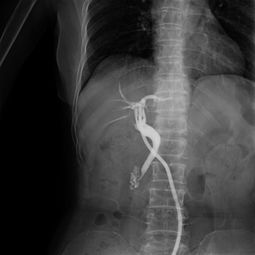

病情分析:您好,造影一般在月經(jīng)干凈后第三天至第五天做,做之前最好是不要性交. 意見(jiàn)建議:做完造影最好是隔一個(gè)月再計(jì)劃懷孕,因?yàn)樽龅臅r(shí)候有照X光.祝心情愉悅.病情分析: 您好,對(duì)于檢查輸卵管是否阻塞通暢,最好是做:動(dòng)態(tài)數(shù)字化子宮輸卵碘油造影響,它是 在全程無(wú)痛的情況下完成的,對(duì)于輕微阻塞的輸卵管能起到疏通治療的作用.并且患 者可以在第一時(shí)間看到自己的輸卵管與宮腔的形態(tài)..若是嚴(yán)重阻塞則需要手術(shù)來(lái)疏通意見(jiàn)建議: 1,必須在月經(jīng)干凈3-7天后檢查,因?yàn)榇似谧訉m內(nèi)膜較薄,不易造成子宮內(nèi)膜異位癥. 2,檢查之前禁止性生活. 3,在造影檢查過(guò)程中注射造影劑后,必須拍片兩次方能確定診斷您好:造影的檢查要在月經(jīng)干凈后的3-7天檢查,輸卵管分間質(zhì)部,峽部,壺腹部,傘端.輸卵管粘連,堵塞,上舉屬于器質(zhì)性的改變,藥物治療沒(méi)有明顯的改變,手術(shù)治療效果明顯,一般可采取宮腔鏡,腹腔鏡,輸卵管鏡治療,創(chuàng)傷小,恢復(fù)快可以在專家的指導(dǎo)下盡快受孕.y病情分析: 您好,很高興為您解答意見(jiàn)建議:造影一般在月經(jīng)干凈后第三天至第五天做,做之前最好是不要同房. 做完造影最好是隔一個(gè)月再計(jì)劃懷孕,因?yàn)樽龅臅r(shí)候有照X光. 生活護(hù)理:祝您早日康復(fù)身體健康您好: 受孕是個(gè)很復(fù)雜的生理過(guò)程.它要求精卵相合形成受精卵,最后著床于宮腔.除了要有正常的精子,卵子和適當(dāng)?shù)淖訉m內(nèi)環(huán)境外,使精子,卵子能夠相遇并順利運(yùn)送到宮腔也是受孕經(jīng)過(guò)中一個(gè)重要的環(huán)節(jié).這個(gè)任務(wù)是由輸卵管來(lái)完成的.如果輸卵管有炎癥,導(dǎo)致輸卵管堵塞,精子不能通過(guò)與卵子相遇造成的不孕,則稱為輸卵管阻塞性不孕.輸卵管根據(jù)形態(tài)由內(nèi)向外分為四部分:間質(zhì)部,峽部,壺腹部,傘部.在臨床上,有80%的不孕癥患者是由于輸卵管因素而造成.輸卵管阻塞常因人工流產(chǎn),自然流產(chǎn),藥流,引產(chǎn),不潔性交,盆腔感染等引起輸卵管壁粘連,充血,水腫而阻塞,導(dǎo)致精子與卵子不能夠結(jié)合,最終導(dǎo)致不孕癥.建議您到??漆t(yī)院就診,明確病情嚴(yán)重程度后在選擇合適的治療方案進(jìn)行疏通.W病情分析: 輸卵管造影前注意事項(xiàng)意見(jiàn)建議: 1,必須在月經(jīng)干凈3-7天后檢查,因?yàn)榇似谧訉m內(nèi)膜較薄,不易造成子宮內(nèi)膜異位癥. 2,檢查之前禁止性生活.3,在造影檢查過(guò)程中注射造影劑后,必須拍片兩次方能確定診斷.。